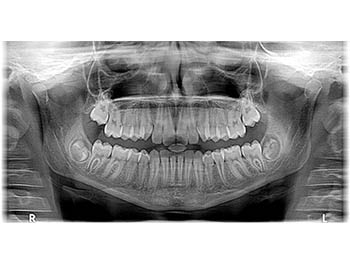

RADIOGRAFIA PANORAMICA

L’Ortopantomografo (panoramico digitale) permette di realizzare radiografie digitali delle intere arcate dentali e dell’articolazione temporo-mandibolare (ATM).

Strumento indispensabile per la diagnosi e pianificazione del trattamento.

La radiologia digitale ha assunto un ruolo fondamentale nella pratica odontoiatrica. E’ uno strumento che consente al medico di identificare con precisione, l’anatomia della struttura maxillo-facciale, valutare il corretto espletamento delle fasi operatorie e verificare i risultati raggiunti alla fine del trattamento.

La radiografia digitale rispetto alla radiologia tradizionale ha apportato numerosi vantaggi: enorme riduzione dell’esposizione dei pazienti alle radiazioni, procedure più semplici, acquisizione dell’immagine in tempo reale, archiviazione molto semplice, rispetto dell’ambiente avendo eliminato qualsiasi materiale di consumo da smaltire come liquidi, lastre, sostanze estremamente inquinanti.